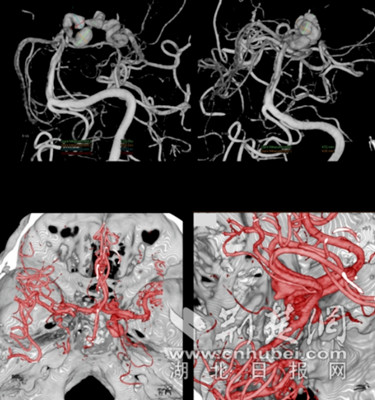

中南医院神经外科第一时间对患者进行详细检查,精准确诊为:大脑后动脉蛇形动脉瘤,蛛网膜下腔出血。这个动脉瘤不规则瘤样扩张,累及大脑后动脉段长,呈“蛇形”并破裂。且动脉瘤紧挨着中脑,是个名副其实的“不定时炸弹”。由于动脉瘤出血时间较长,患者大脑正处于水肿高峰期,颅内血管也处于痉挛状态,给本来就很复杂的手术增加了很大难度。科室马上争分夺秒周密研究治疗方案。

呈蛇形的动脉瘤 通讯员供图